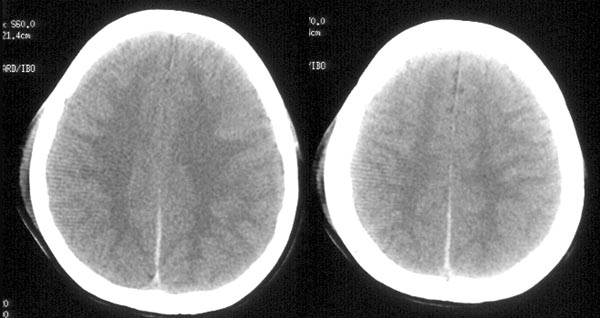

女性,18岁。车祸致伤头部3小时。

ct平扫:左颞骨内板下见细线形高密度出血影,左侧侧脑室受压变窄,中线结构向右侧移位。大脑镰、小脑幕及左枕部脑沟密度增高。鞍上池、环池均显示不清。

ct诊断:1、左颞硬膜下血肿。

2、蛛网膜下腔出血。

3、脑肿胀。